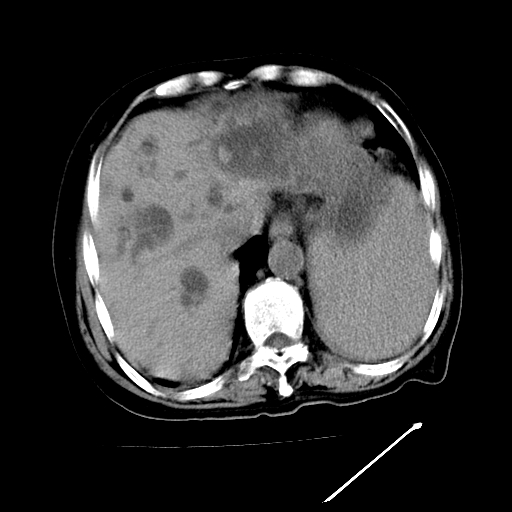

以下是引用随光逐影在2009-4-7 8:21:00的发言:[br]肝内外胆管多发性结石并肝内外胆管扩张;胆系感染。